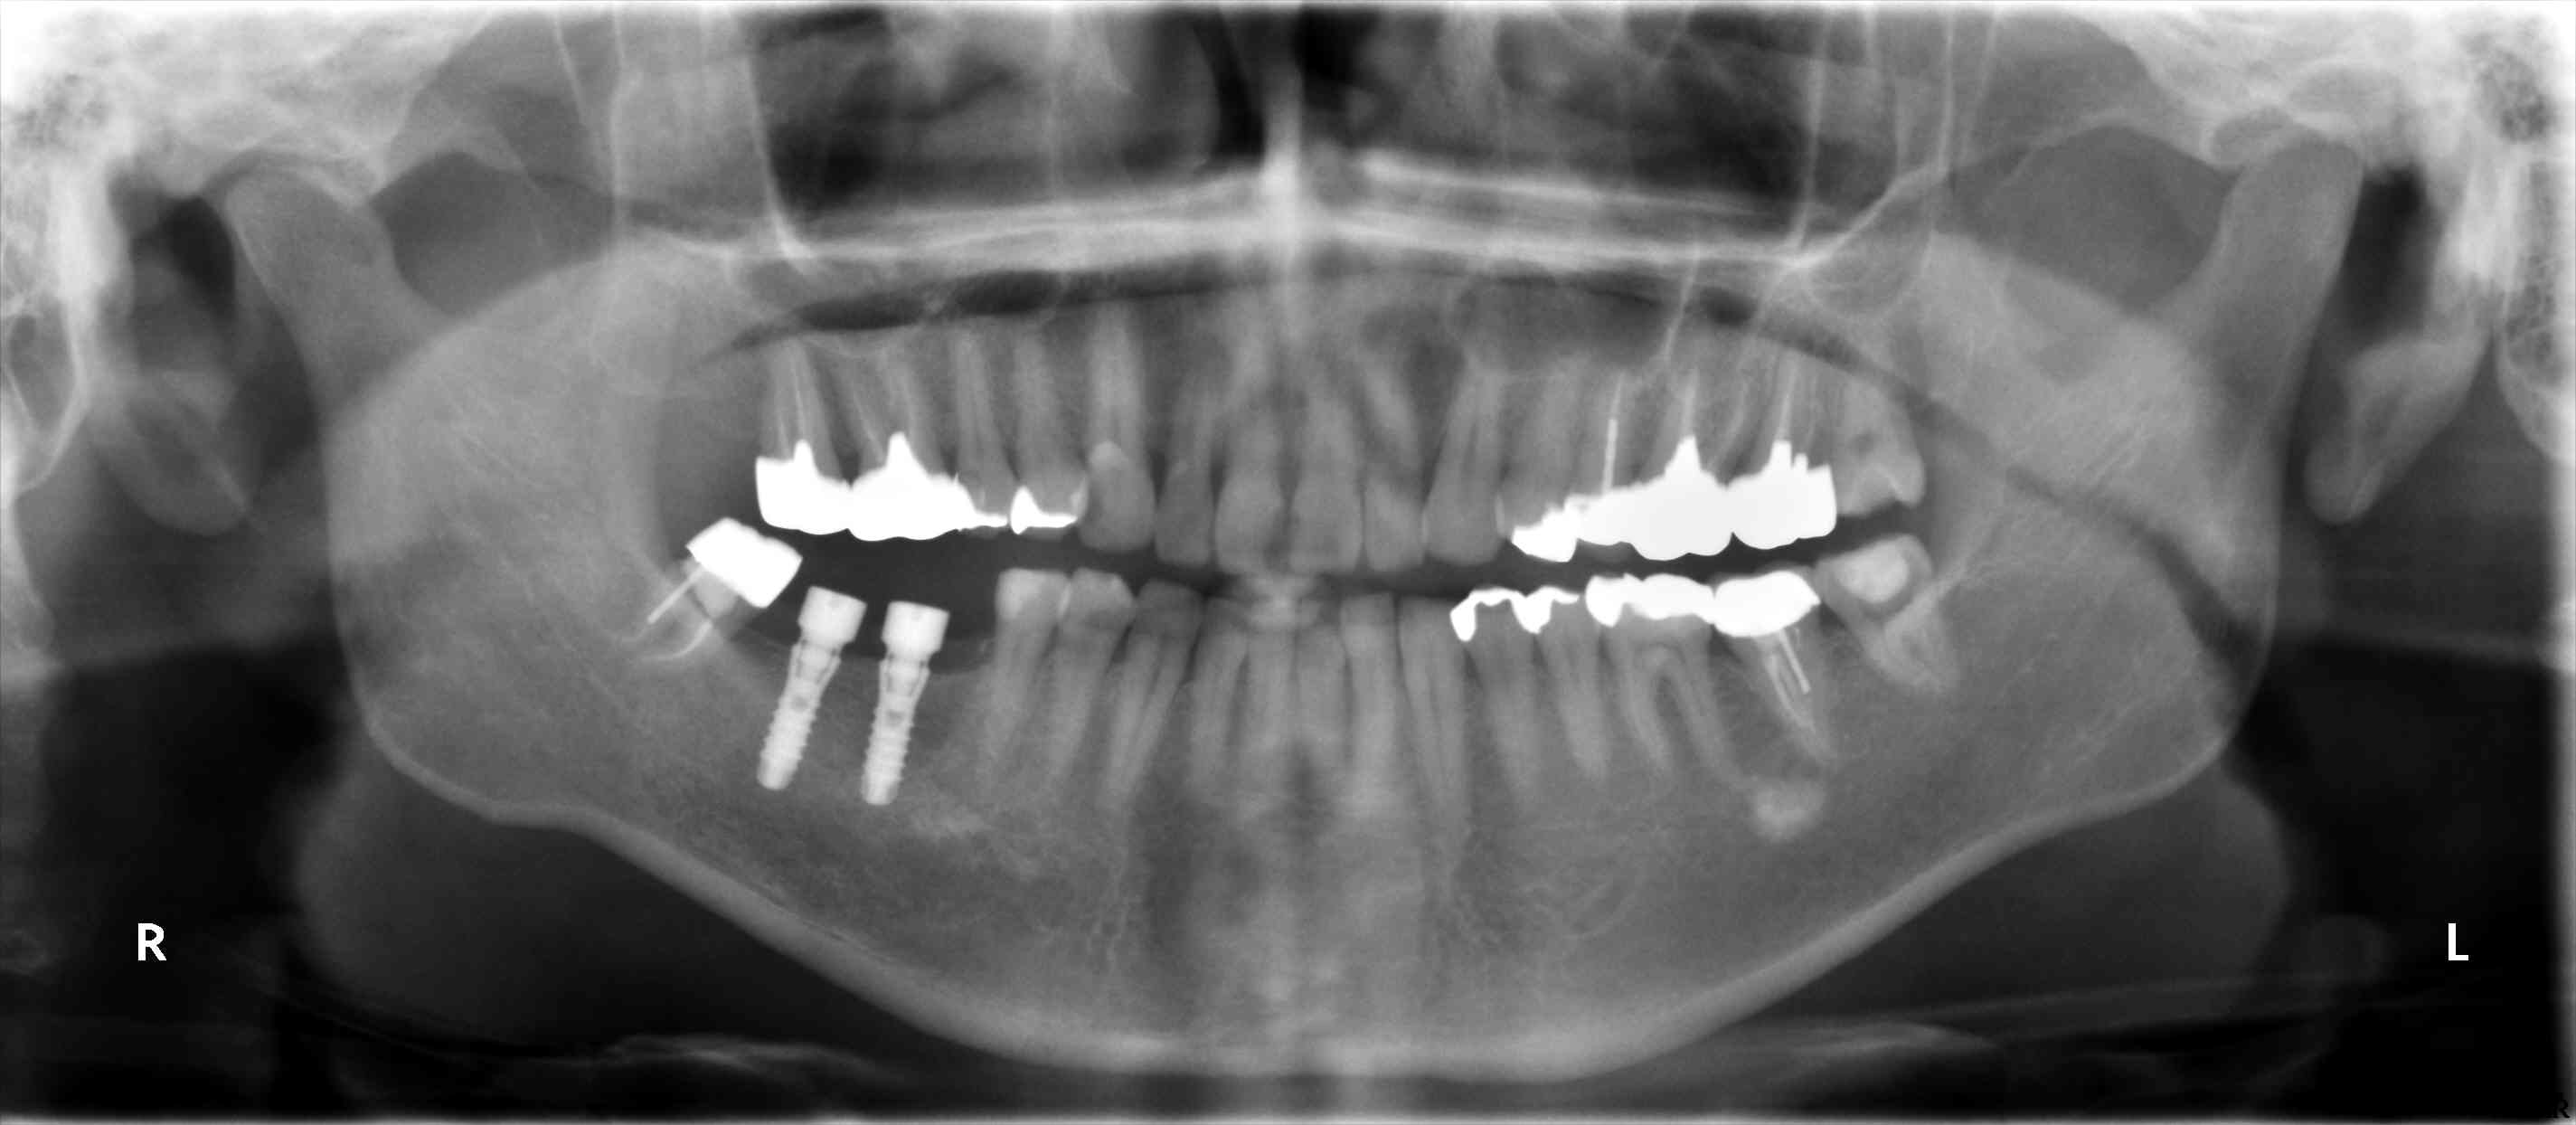

術後のパノラマです。

今日は、右下67部位の成熟側に2本のサイブロンプロEXRN13mmを埋入しました。

骨幅、深さも十分でしたので、気を付けたことは、オペ時間を短くするということと、埋入位置を正確にするということくらいでした。

歯槽頂に骨の増殖がみられましたので、ドリリング前にマイセルで削除しました。

初期固定も強固にできて、プラットフォームスイッチ用のアバットメントを装着して1回法で終了しました。